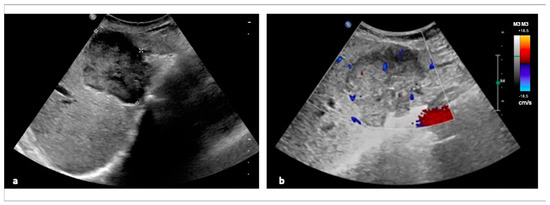

2.1. Ultrasonography (US)

- Guo, L.H.; Xu, H.X. Contrast-Enhanced Ultrasound in the Diagnosis of Hepatocellular Carcinoma and Intrahepatic Cholangiocarcinoma: Controversy over the ASSLD Guideline. Biomed. Res. Int. 2015, 2015, 349172. [Google Scholar] [CrossRef]

- Hennedige, T.P.; Neo, W.T.; Venkatesh, S.K. Imaging of malignancies of the biliary tract- an update. Cancer Imaging 2014, 14, 14. [Google Scholar] [CrossRef]